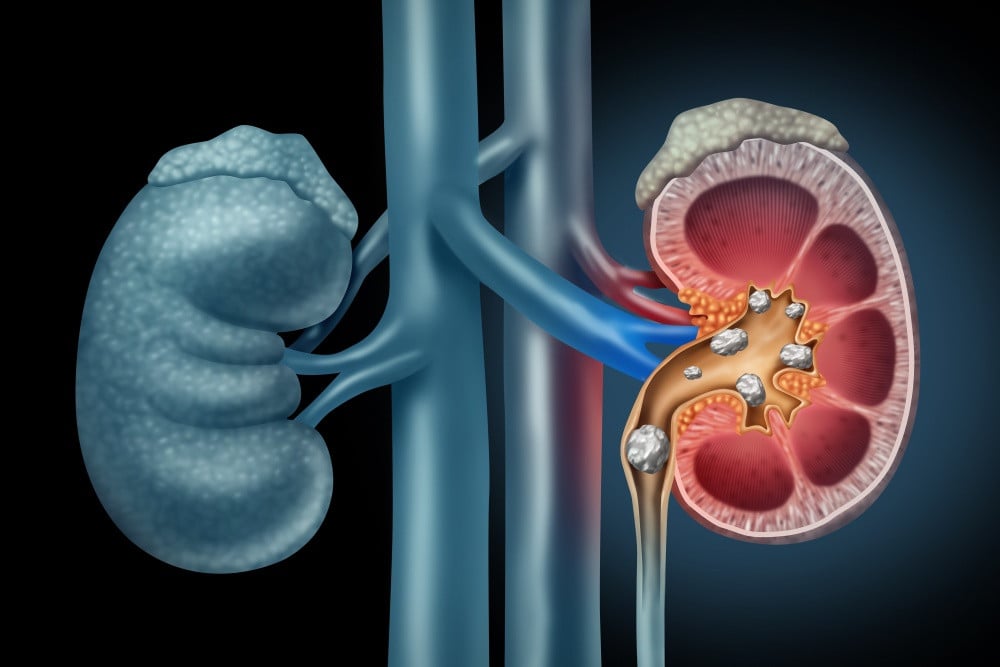

Ginjal memegang peranan penting dalam menjaga keseimbangan cairan dan mineral tubuh sekaligus menyaring darah dari limbah dan racun. Namun, berbagai faktor seperti pola hidup tidak sehat, konsumsi alkohol, dan faktor genetik dapat mengganggu fungsi ginjal sehingga berisiko menyebabkan Penyakit Ginjal Kronis (PGK). Meskipun PGK tidak bisa disembuhkan, pola makan yang tepat dapat membantu mendukung kesehatan ginjal dan mencegah kerusakan lebih lanjut.

Beberapa makanan sehari-hari telah terbukti secara alami dapat membantu detoksifikasi ginjal, meningkatkan fungsi organ vital ini, dan mengurangi risiko batu ginjal. Berdasarkan data dari University Health, berikut lima jenis makanan yang efektif untuk menjaga kesehatan ginjal.

Lemon mengandung asam sitrat yang berperan dalam pencegahan batu ginjal dengan cara meningkatkan produksi urine dan menurunkan keasaman dalam tubuh. Ini membantu menjaga tubuh tetap dalam kondisi basa dan memecah batu ginjal kecil sehingga tidak berkembang lebih besar. Vitamin C dalam lemon juga memberikan perlindungan antioksidan yang penting untuk menjaga integritas sel ginjal.